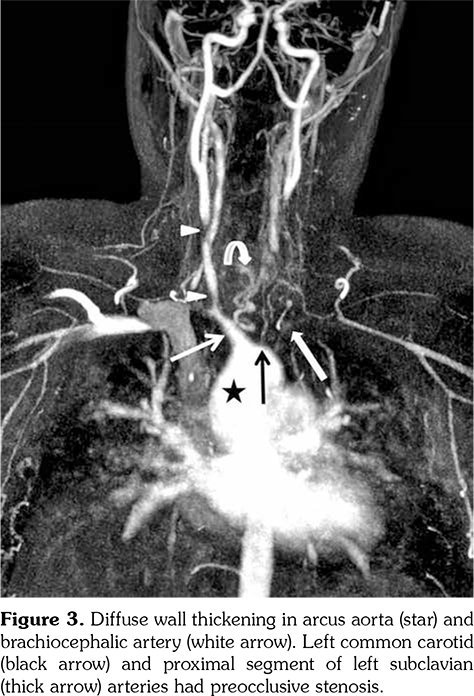

A 14-year-old female patient referred to our clinic with headache and dizziness for two weeks and loss of consciousness for about 10 minutes. On admission, the blood pressure was 90/60 mmHg and all peripheral pulses were palpable. Her body weight was above 97th percentile for her age and body mass index was 33. The fundus examination and other organ systems were essentially normal. Laboratory studies revealed erythrocyte sedimentation rate (ESR) as 108 mm/hour and C-reactive protein (CRP) as 7.5 mg/dL (0-0.8), while other measurements were normal. Urinalysis revealed microscopic hematuria and proteinuria of 31.9 mg/m2/hour in 24-hour urine collection. The cerebrospinal fluid examination showed no abnormalities. Cranial magnetic resonance imaging (MRI) showed multiple millimetric hyperintense deep white matter lesions on T2-weighted imaging (Figure 1). Intracranial and extracranial arteries were normal in magnetic resonance angiography (MRA). Renal biopsy findings were interpreted as FSGS (Figure 2). Patient was considered as cerebral vasculitis and incidental FSGS. Pulse methylprednisolone therapy for three consecutive days was initiated and continued with oral prednisolone. At four years of follow-up, proteinuria decreased to 5-15 mg/m2/hour, and ESR and CRP were normal. Repeated brain MRI and MRA examinations showed no new lesions. Four years later, at the age of 18, on a routine examination, both radial artery pulses were absent and the blood pressure could not be measured. Significant bruit was heard on the left carotid artery. Laboratory studies revealed ESR as 43 mm/hour and CRP as 2.46 mg/dL. Aortic MRA revealed diffuse wall thickening and contrast enhancement in the arcus aorta and its many main branches (Figure 3). Takayasu arteritis diagnosis was established according to the European League Against Rheumatism/ Paediatric Rheumatology International Trials Organisation/Paediatric Rheumatology European Society criteria.[2] Methotrexate was begun, and daily prednisolone was continued. Four months after the diagnosis of TA, left-sided hemiparesis developed. Brain MRI demonstrated a wide cerebral infarct at the right anterior vascular territory (Figure 4). Brain and neck computed tomography angiography showed total occlusion of the right internal carotid artery. Vascular involvement of the right common carotid artery was progressed to preocclusive stenosis. Diameters of the right anterior and middle cerebral arteries were thin and fed by the posterior and anterior communicating arteries (Figure 5). Tocilizumab treatment was started at 8 mg/kg every four weeks. At follow- up with 2.5 years of tocilizumab treatment, the patient's clinical condition improved slightly, and no new symptoms developed. A written informed consent was obtained from the patient.